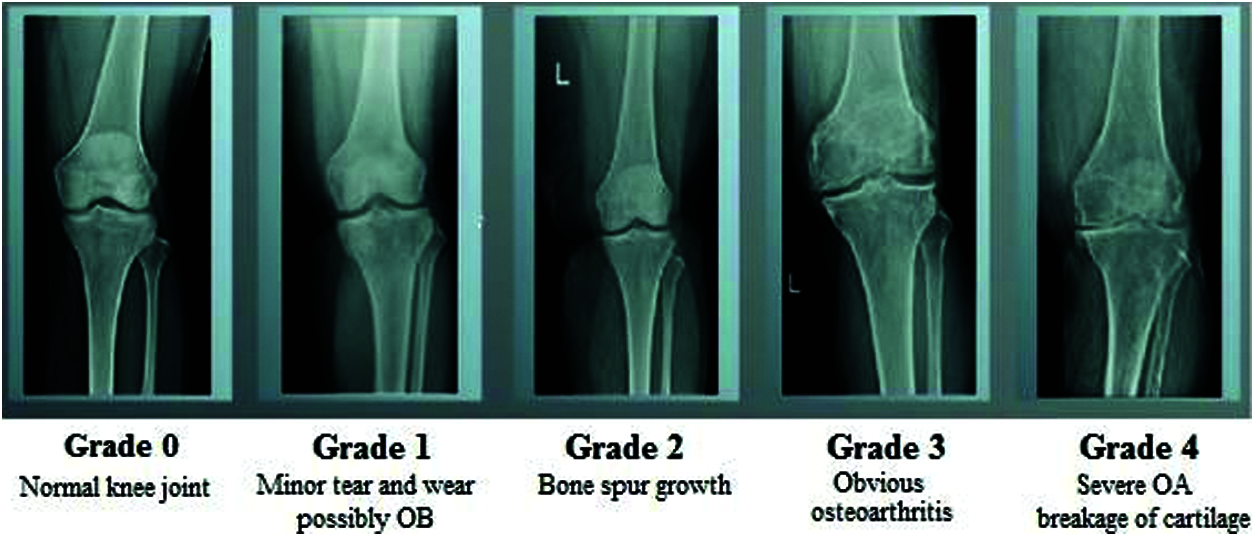

The human skeletal system is a persistent framework that plays a key role in retaining the shape of the body and enabling its movement. Joints are the points where bones are connected for Osteoarthritis Disease Diagnosis to a layer of soft tissue known as ligaments [1]. Ligaments are fibrous connective tissues that form a thin layer over the junction of joints to prevent friction between the bones and prevent abnormal movement [2]. The application of excessive stress for long periods gradually reduces the strength of the ligaments and causes arthritis. Osteoarthritis (OA) is a widely known joint disorder that occurs when soft tissues between the joints degenerate owing to prolonged stress [3]. In general, OA affects the joints in the hands, knees, spinal region, and ankles. Chronic OA consists of four stages: minor, mild, moderate, and severe [4]. Several therapeutic techniques have been developed to treat OA. The early detection of the degradation of the cartilage can prevent eventual disability in the patient [5]. Image processing is an efficient technique for identifying the different stages of osteoarthritis. Various classification processes have been developed to identify the stages of osteoarthritis of the knee. The general radiological technique, X-ray, is commonly used to visualize the knee to analyze changes in it during the early stages of OA. MRI, CT, and ultrasound have also shown promising results for the identification of OA, but X-rays are more reliable, easier to obtain, and accurate at identifying OA in joints of the knee. Fig. 1 shows the different stages of the osteoarthritis of the knee.

Figure 1: Different stages of osteoarthritis

1.1 Arthritis in Knee: Four Stages of Osteoarthritis

OA is a kind of joint disorder. Specialists claim that half of all people eventually build up some kind of suggestive OA in their lives. It can influence the hips, hands, and shoulders, and usually occurs in the knees. Fig. 3 shows a normal knee and one affected by OA. OA got progressively can be treated, where identifying it in the early stage is important for successful treatment [14]. The four phases of OA in each stage are discussed below.

• The first stage (Class 0) is considered normal with minor abnormalities. This is the most benign phase of OA, and patients experience a negligible amount of pain.

• The second stage (Class 1) is mild. This is the first stage in which bone spur enlargement can be observed through X-ray. The exaggerated region becomes rigid after extensive periods of inactivity, and becomes painful.

• The third stage (Class 2) is moderate; the cartilage in the exaggerated region begins to wear away. The joint swells up, and the patient experiences discomfort in everyday movements [15].

• The fourth stage (Class 3) is severe. The pain increases, and nearly the entire cartilage moves to create a provocative reaction that starts in the joint and causes extreme pain.